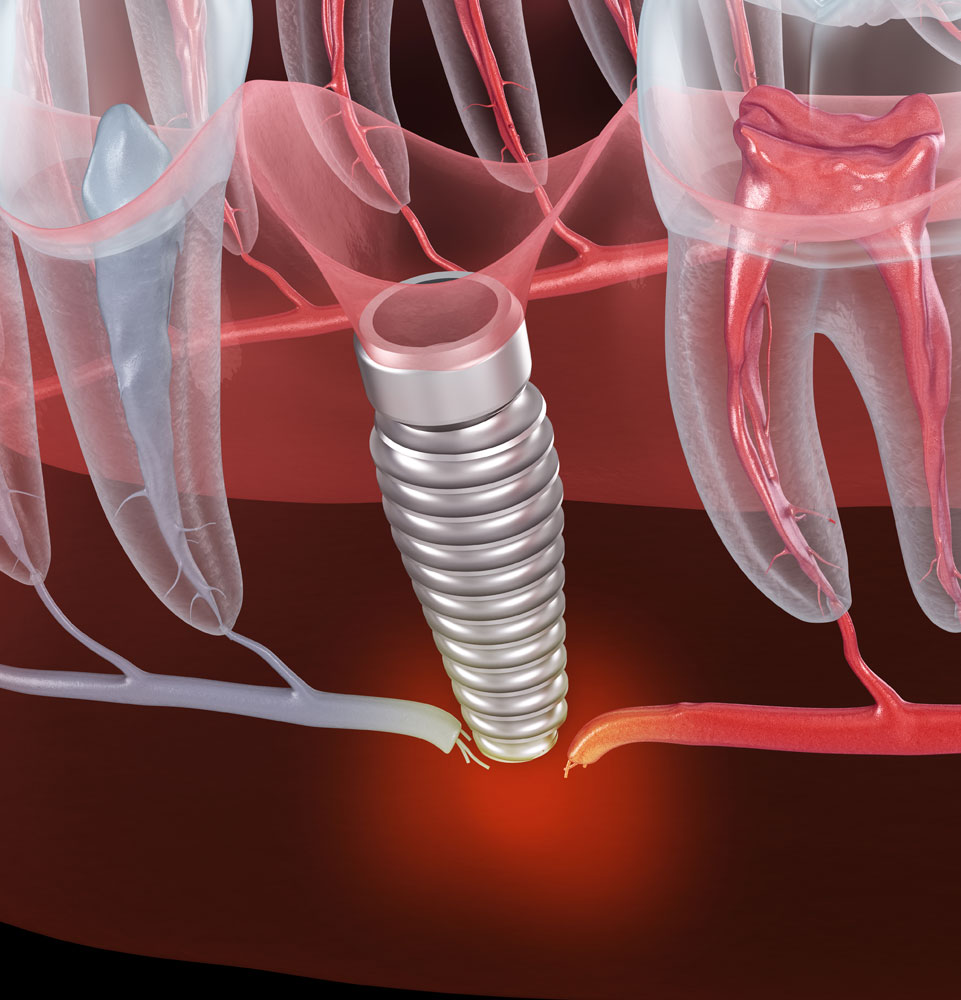

As a tooth replacement method, dental implants are unmatched. They look, feel, and function just like natural teeth. Nothing does a better job of restoring your quality of life or self-confidence. They also boast a success rate of 98%! However, under certain circumstances, dental implants may still fail.

Prior failed grafting procedures, bad extractions, bad bridgework, and improper placement are potential factors. Peri-implantitis is the leading cause. Fortunately, you can avoid this condition (more at the bottom of this page). If you have failing dental implants in Flower Mound and Denton, TX, come to the experts at the Texas Center for Oral Surgery and Dental Implants.

We know implants. In fact, we’ve placed 2,000 of them and counting. As board-certified oral and maxillofacial surgeons, we’re dental implant specialists, with years of specialty training beyond dental school.

General dentists can offer dental implant care, but they lack the surgical background that enables us to handle the most complex cases. We’re trained for them. If you’ve had dental implant complications—including peri-implantitis—we can help restore and protect your smile for many years to come.